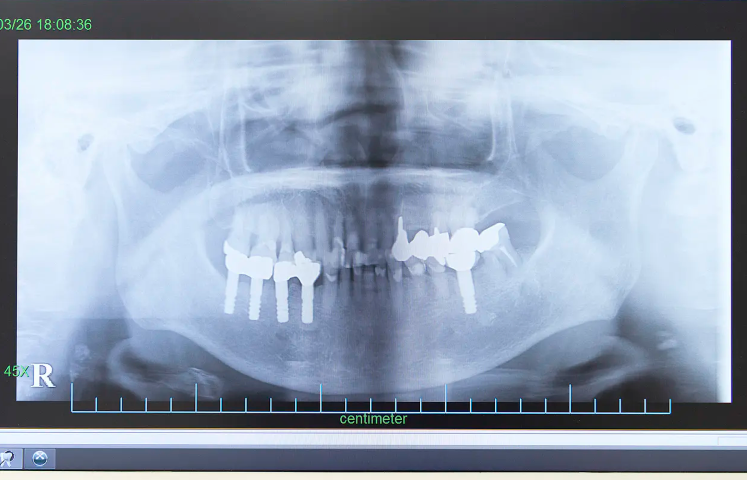

安心・安全を第一に、大学病院の経験を活かしたインプラント治療

中川歯科医院では、神戸大学附属病院で口腔外科の経験を積み、インプラント治療に20年以上携わってきた院長が、すべての症例を担当しています。外科手術を伴うインプラント治療は高度な技術と正確な診断が求められる分野であり、実績豊富な歯科医師による対応が安心感に直結します。

治療前には歯科用CTを用いて、あごの骨や神経、血管の位置を3次元で立体的に把握。患者様のお口の状態を正確に診断し、リスクを最小限に抑えた治療計画を立案します。また、治療後もインプラントのメインテナンスを丁寧に行い、長期的にトラブルのない使用を目指します。